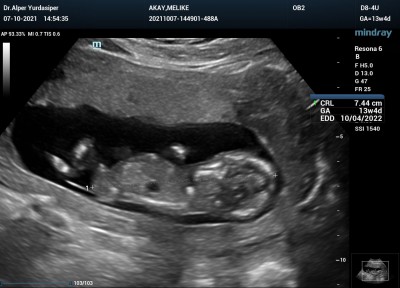

Kızlar detaylı ultrason merkezinde bir radyoloji uzmanı tarafından muayene edildim. İlk önce %99 kız daha sonra %99 erkek dedi. Bacak arasında kordon vardı.  Kafam allak bullak doktor kontrolüne bir hafta var.. Tahmin yürütebilen var mı acaba ya ?

Gebelik haftası 13+6